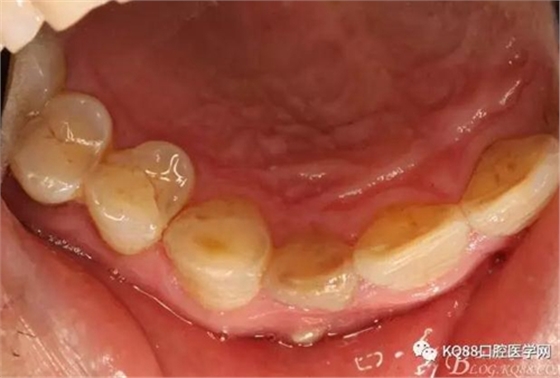

圖2. 12牙齒在我院進(jìn)行熱牙膠根管充填+樹(shù)脂充填。

一個(gè)月后患者復(fù)查: 唇側(cè)觀:11根尖區(qū)粘膜有一膿瘺,捫診溢膿,牙冠成灰褐色。根管治療無(wú)法治愈根尖病變,建議根管外科治療,患者同意手術(shù)。